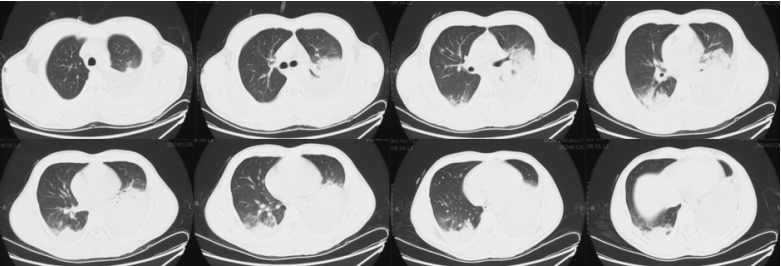

复查胸部CT(入院前3天/入院前2天):双肺炎症性病变,下肺实变呈加重趋势,右下肺有新发实变影(图2,图3)。患者影像学从单叶进展为多叶多段病变,渗出影进展非常快。左下肺影像学表现与大叶性肺炎不同,大叶性肺炎通常伴有支气管充气征,但该患者影像学完全无支气管充气征。对比患者三次影像学表现可见病变进展异常迅速。纵隔窗也提示患者病变迅速进展,且实变中未见支气管气相。

图片

图2  患者外院胸部CT(入院前3天)

图3  患者外院胸部CT(入院前2天)